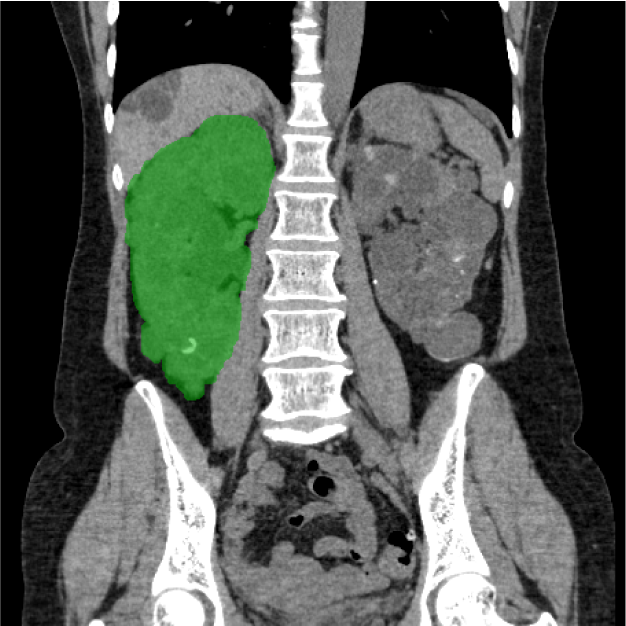

CANON(旧:東芝)社製の80列マルチスライスCTを設置し、胸部・腹部の撮影はもちろん、心臓CTや大腸CT、下肢3DCTといった専門性の高い撮影も行っています。最新のザイオワークステーションを用いて、3D画像作成、心臓解析、大腸の仮想内視鏡検査などを行っています。また、近隣の医療施設からのCT撮影依頼にも対応しており、日々たくさんご利用いただいております。被ばく線量の低減に配慮するとともに、患者さんに合った適切な線量で撮影を行うように心がけています。

腰椎CT画像 腎臓CT画像